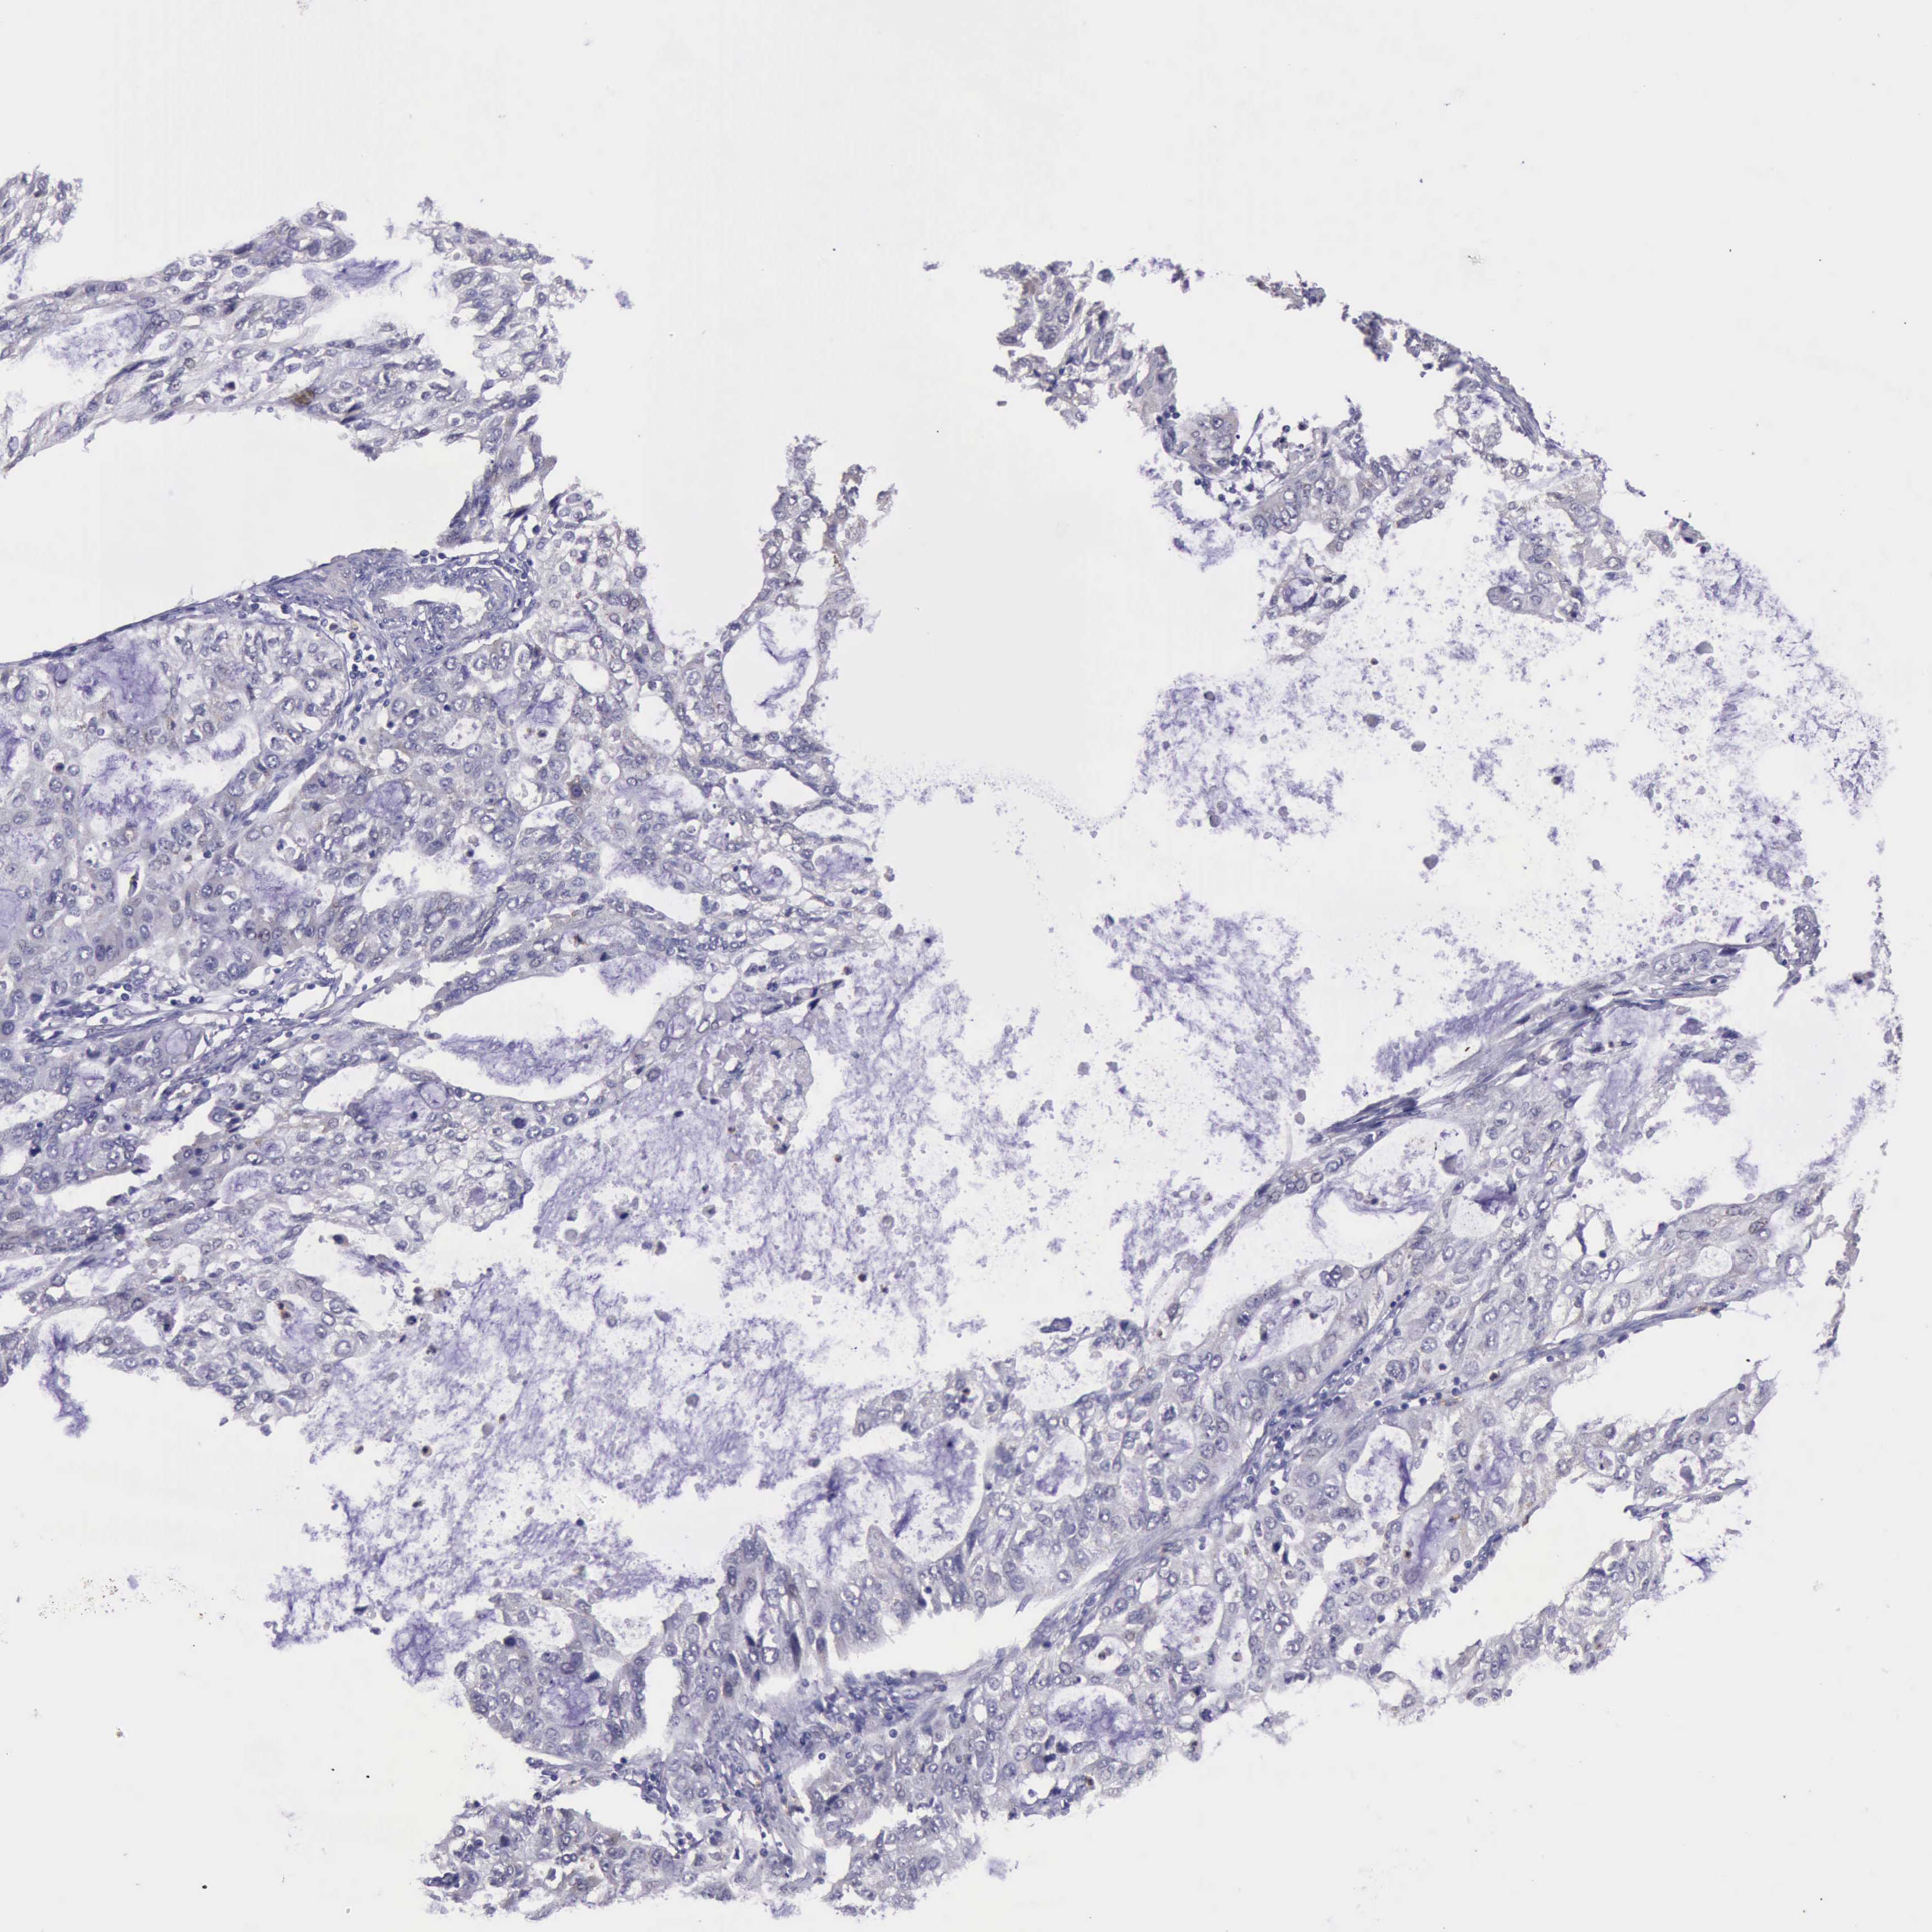

STOMACH CANCER - Protein expressioni

A mouse-over function shows sample information and annotation data. Click on an image to view it in a full screen mode. Samples can be filtered based on level of antibody staining by selecting one or several of the following categories: high, medium, low and not detected. The assay and annotation is described here.

Antibody stainingi

Antibody staining in the annotated cell types in the current human tissue is reported as not detected, low, medium, or high, based on conventional immunohistochemistry profiling in selected tissues. This score is based on the combination of the staining intensity and fraction of stained cells.

Each image is clickable and will lead to virtual microscopy that enables deeper exploration of all samples and also displays staining intensity scores, fraction scores and subcellular localization as well as patient and tissue information for each sample.

Antibody HPA001208

Staining

High

Medium

Low

Not detected

Intensity

Strong

Moderate

Weak

Negative

Quantity

>75%

75%-25%

<25%

None

Location

Nuclear

Cytoplasmic/membranous

Cytoplasmic/membranous,nuclear

Adenocarcinoma, NOS